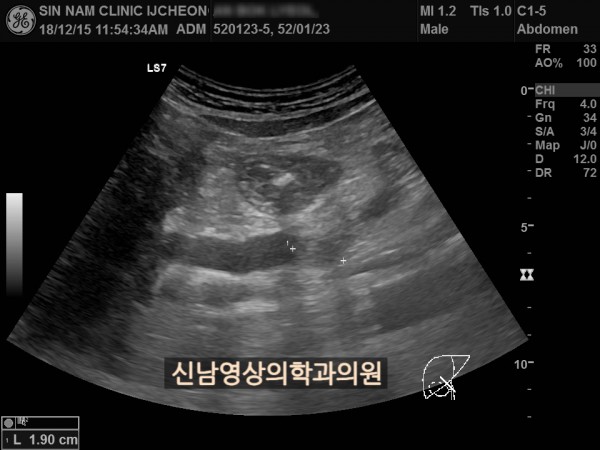

상복부 초음파 적용 사례

본 환자분은 50대 중반의 남성분으로 손가락안이 가렵다는 느낌으로 내원하셨습니다.